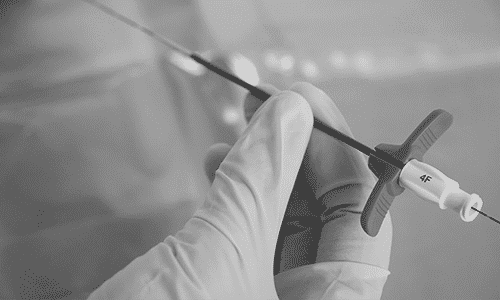

Video explicativo en el que se ve de forma práctica cómo insertar un catéter de línea media mediante la técnica Seldinger sin dilatación (Seldinger pura)

Técnica de inserción Seldinger pura